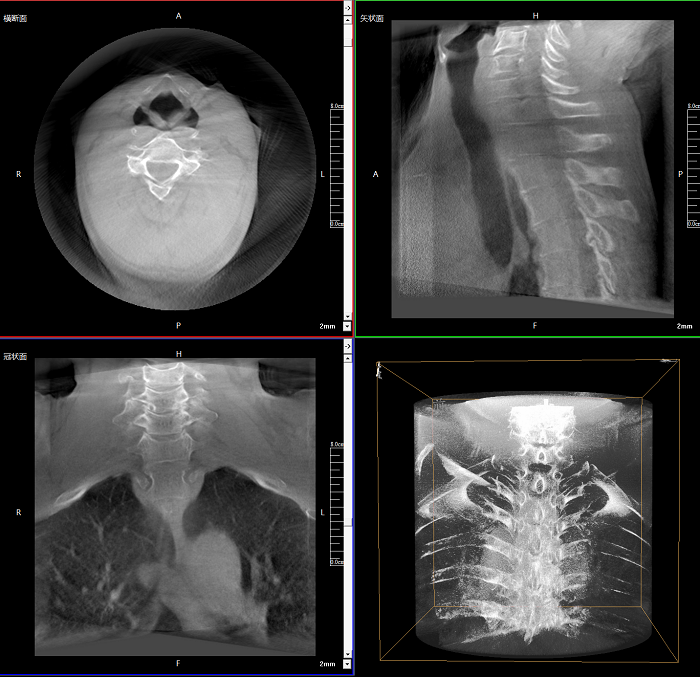

三維成像 全面觀察

任意視角、任意切面觀察

術(shù)中實(shí)時(shí)生成橫斷面、矢狀面、冠狀面及三維影像,可在任意切面、任意角度評(píng)估植入物和解剖結(jié)構(gòu)的相對(duì)位置。